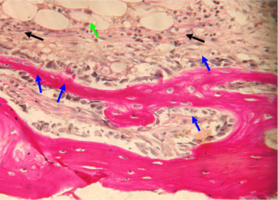

При большем увеличении (х400) на препаратах отмечается бурная пролиферация клеток соединительной ткани и макрофагально-моноцитарного ростка крови.

Тканевые макрофаги окружают фрагменты спонгиозы и осуществляют их активную резорбцию.

Клетки соединительной ткани (фибробласты) участвуют в синтезе коллагеновых волокон, и активно внедряются в поры и ячейки имплантированного материала (рис. 3).

Рис. 3. Нижняя челюсть кролика через 14 суток после остеопластики слева, смесь лиофилизированной аллоспонгиозы и ГАП 1:1.

Синими стрелками указан фрагмент аллогенной спонгиозы, подвергающийся активному лизису макрофагами (указаны черными стрелками).

Окраска - пикрофуксин по ван Гизон, х400.